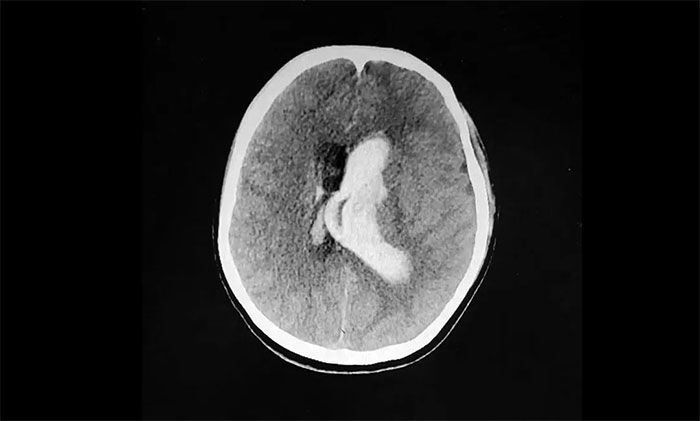

情急之下,家人匆忙将她送到附近医院。经头颅CT检查显示:脑室出血,左侧脑室、三、四脑室铸型。

▲ 突发性脑出血,左侧血肿已突入脑室

脑出血往往起病突然,进展迅速。病情与出血部位、出血量及并发症有关,致死率很高,急性期为30%-40%。而脑室出血铸型为脑出血中重症类型,其往往出血量大,位置深在,病情危急,病死率相当高。